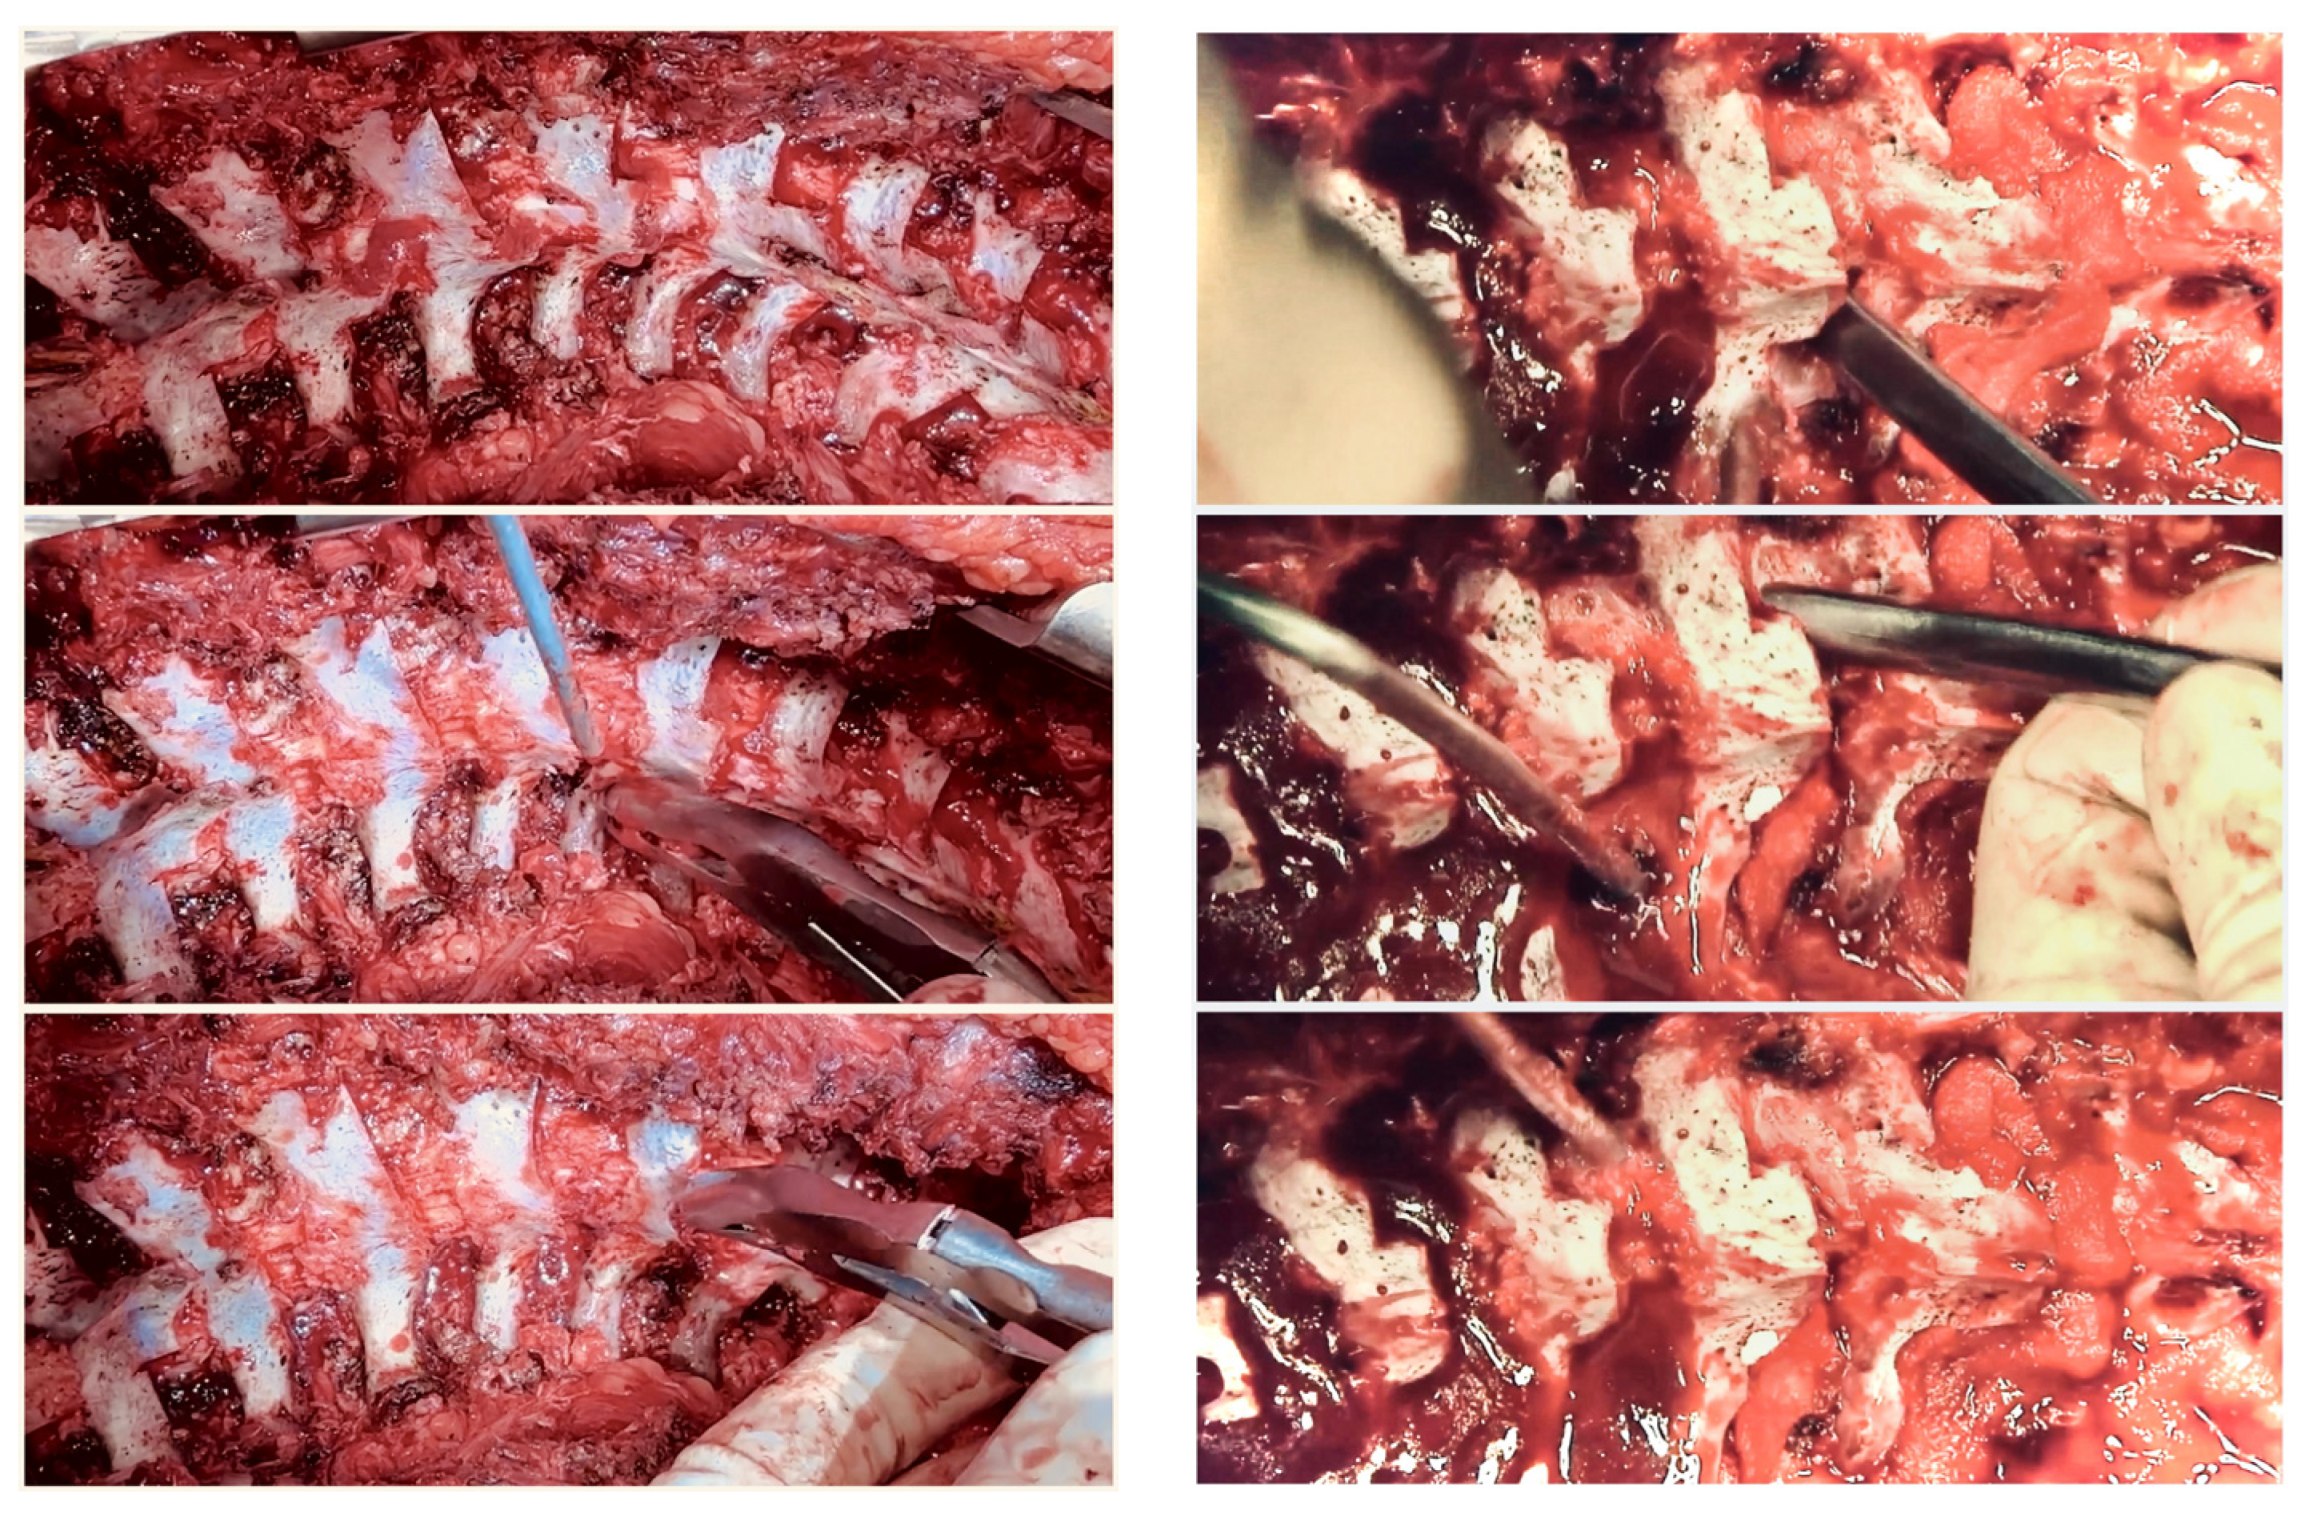

6. Anterior Release

7. Posterior Release

9. MCGR as Temporary Internal Traction

10. Rib Resection/Thoracoplasty